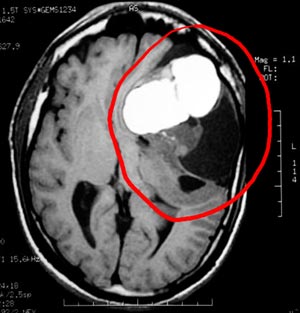

2b) Teratoma maduro

Figura 46 - Ressonância nuclear magnética antes da cirurgia